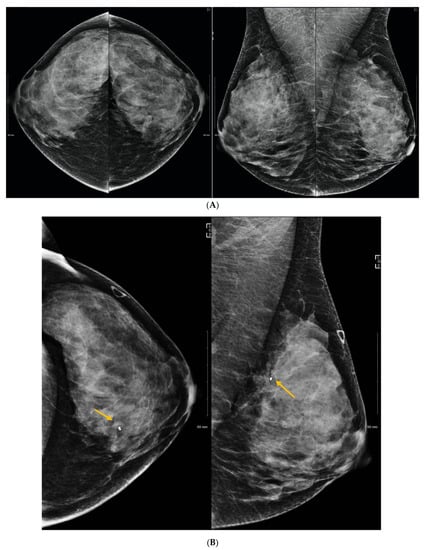

6. Digital Breast Tomosynthesis (DBT)

7. Magnetic Resonance Imaging (MRI)